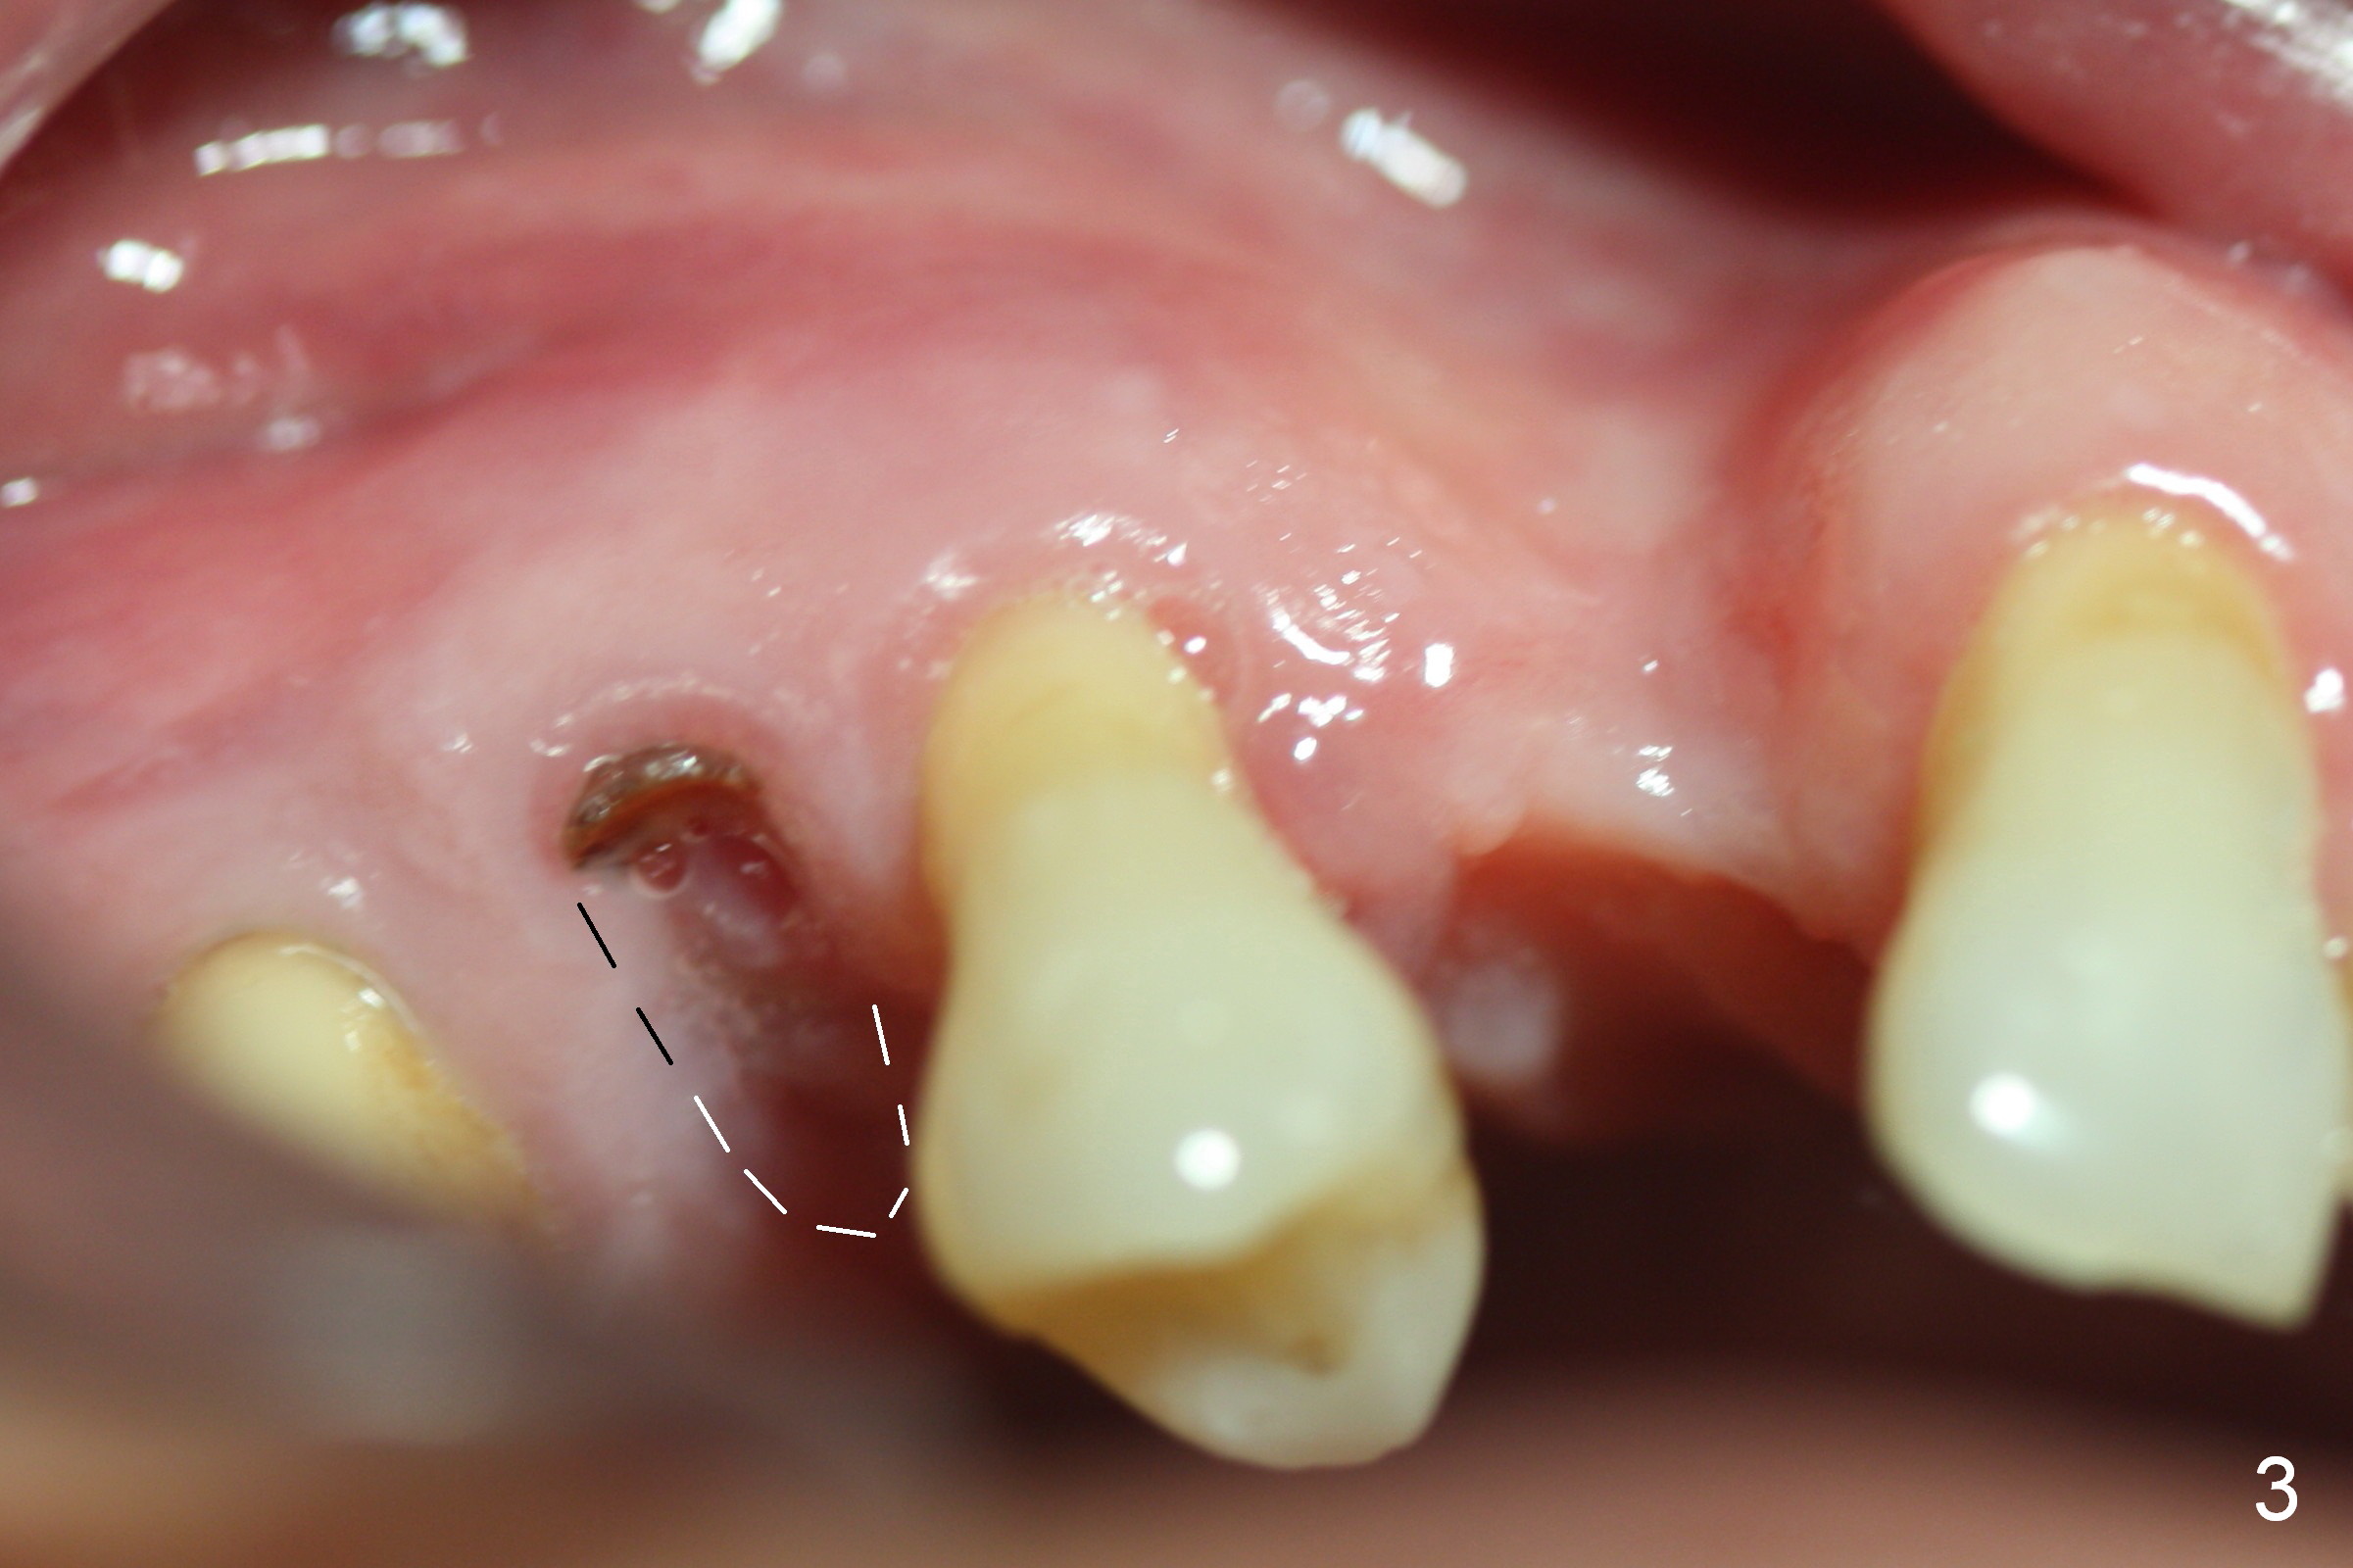

A 62-year-old man (CZ) has had chronic periodontitis. A month ago, five immediate implants were placed in the lower anterior region. Fig. 1 shows a PA taken 4 years ago: #4 residual root and #6 severe bone loss. A 4.1x14 mm bone-level implant is planned immediately after extraction (Fig.2). Clinically, the residual root is oval in shape (Fig.3 dashed line). The implant is placed as palatal as possible after socket treatment with 2% Xylocaine/1:50,000 Epinephrine (Fig.4). In addition, the osteotomy may have to be established in the distal wall, since the root tip tilts mesially (Fig.1). Take the 1st intraop PA after 2 mm pilot drill.